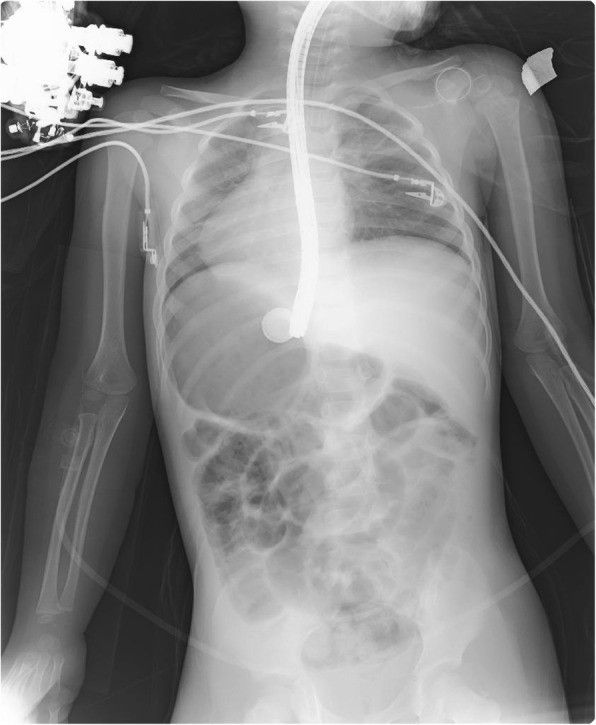

Девочка была госпитализирована с жалобами на боли в животе. При рентгенографии органов брюшной полости в области дна желудка выявлена литиевая батарея (CR 2025, рис. 1).

Рисунок 1 [1].